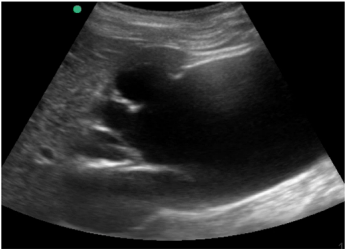

Um paciente de 72 anos de idade foi para a Unidade de Terapia Intensiva (UTI). Institucionalizado, com duas internações nos últimos seis meses por conta de sepse de foco urinário. Na admissão, realizou ultrassonografia abdominal com o achado demonstrado na imagem apresentada. Os exames laboratoriais mostraram ureia = 230, creatina = 10 e potássio = 7,5.

Um paciente de 72 anos de idade foi para a Unidade de Terapia Intensiva (UTI). Institucionalizado, com duas internações nos últimos seis meses por conta de sepse de foco urinário. Na admissão, realizou ultrassonografia abdominal com o achado demonstrado na imagem apresentada. Os exames laboratoriais mostraram ureia = 230, creatina = 10 e potássio = 7,5.

Um paciente de 72 anos de idade foi para a Unidade de Terapia Intensiva (UTI). Institucionalizado, com duas internações nos últimos seis meses por conta de sepse de foco urinário. Na admissão, realizou ultrassonografia abdominal com o achado demonstrado na imagem apresentada. Os exames laboratoriais mostraram ureia = 230, creatina = 10 e potássio = 7,5.